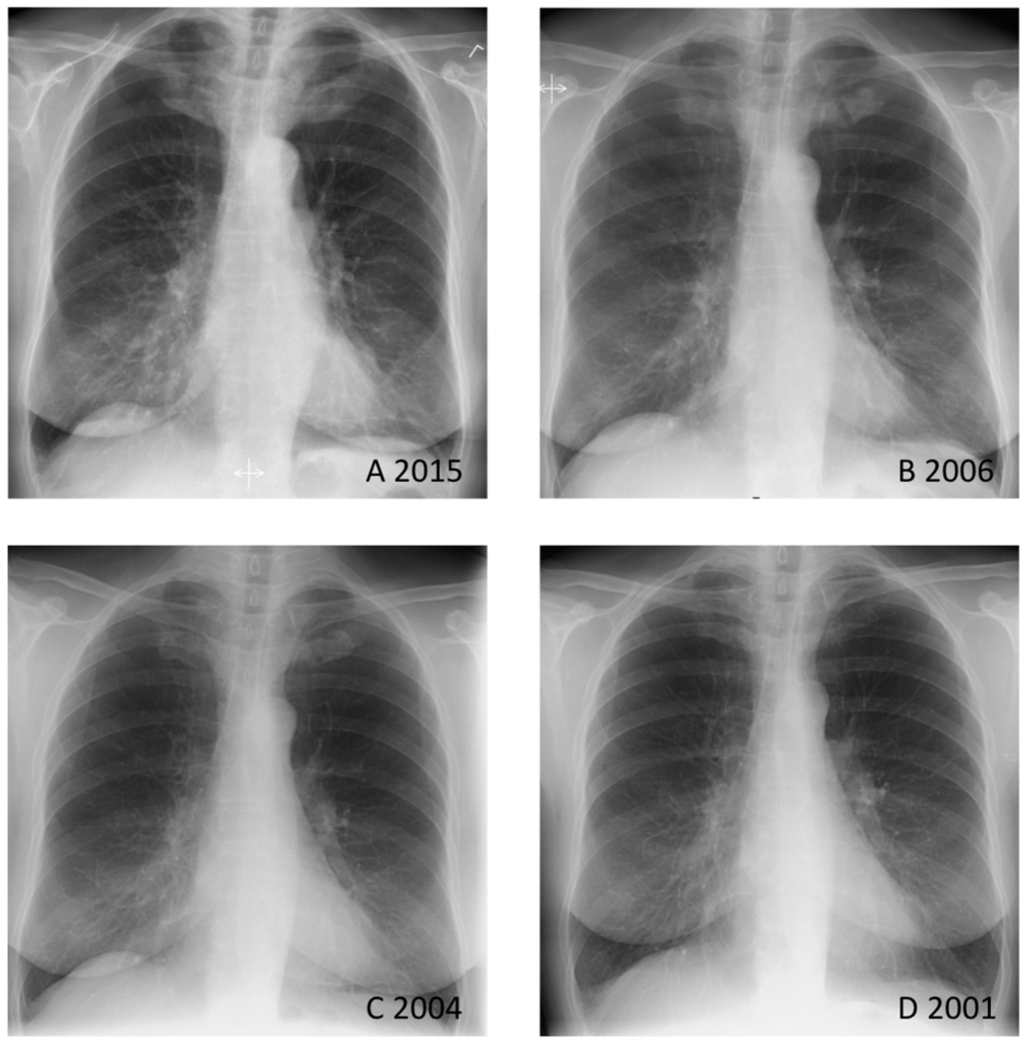

Figure 1. The patient was a healthy 73-year-old woman suffering from intermittent pain in the upper part of the sternum over several years. A chest radiograph from 2015 showed marked bilateral sternocostoclavicular hyperostosis (SCCH) (A); Retrospectively, chest radiographs from 2006 (B) and 2004 (C) revealed that sternocostoclavicular sclerotic changes had already begun—especially when compared with a chest radiograph from 2001 (D). Sternocostoclavicular hyperostosis (SCCH) was described for the first time in Europe in 1975 [1]. Shortly thereafter, in 1977, two new patients presented with the same symptoms of painful swelling of the sternum, clavicles, and upper ribs [2]. In the years to come SCCH was observed in patients in association with various skin lesions, and in 1987 the acronym SAPHO (synovitis, acne, pustulosis, hyperostosis and osteitis) was proposed [3]. Today, SCCH is widely considered to be part of the SAPHO syndrome. SAPHO describes the association between osteoarticular and dermatological lesions, and SCCH is only one of many entities which constitutes SAPHO [4,5,6]. In this patient case, no skin lesions were observed, suggesting SCCH as an isolated entity.